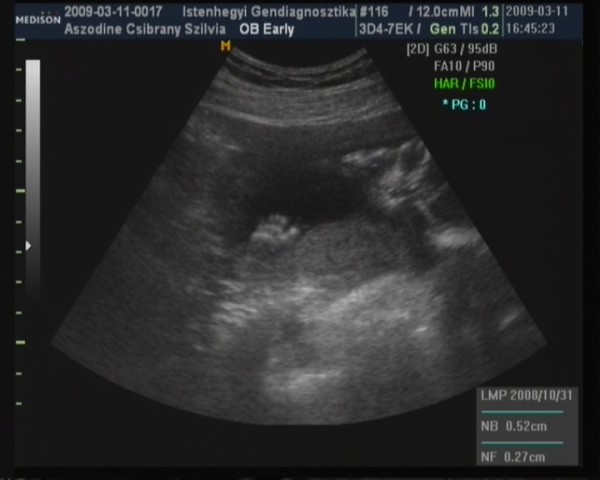

Teszek fel pár képet a drágámról. Kép a kis talpa:)) Kép Kép itt sajna kevésbe látszik az arca

Örülök, hogy minden rendben. Sajnos tényleg elég homályos a kép.

Szerintem változtasd meg a vonalzód, mert ezután már csak méretbeli különbségek lesznek, a kora attól nem változik.